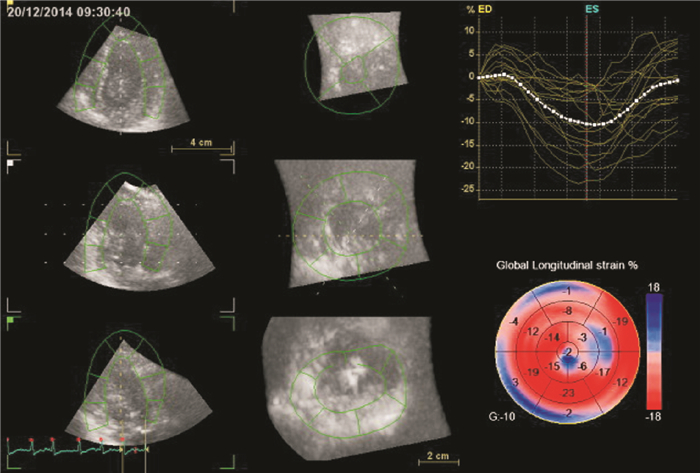

2.3.5 兩組RT-3DE左心室17節段縱向應變牛眼圖

牛眼圖能更直觀地看到兩組差異。圖 1顯示對照組于該圖的右下部牛眼圖大部分為紅色。風濕性二尖瓣狹窄組某患者縱向應變值顯示為基底段(前壁、下壁、下側壁)、中間段(部分前間隔、后間隔)、心尖段(間隔、下壁)及部分心尖應變值減低(圖 2),說明以上節段因心肌纖維化后缺血,心肌運動減弱,顏色變淺甚至變藍。而且右上部為該患者部分節段的應變-時間曲線走行不規整,在整個心動周期中脫離了其余正常心肌的應變-時間曲線的走行方式,且應變值的范圍處于0~6之間。

注:圖 1所示對照組于該圖的右下部牛眼圖大部分為紅色,右上部分為17條節段縱向應變-時間曲線(黃色)及1條左室整體縱向應變-時間曲線(白色),右下部分是以牛眼圖形式顯示的左室收縮末期縱向應變值,牛眼圖左下方的“G”代表整體應變值